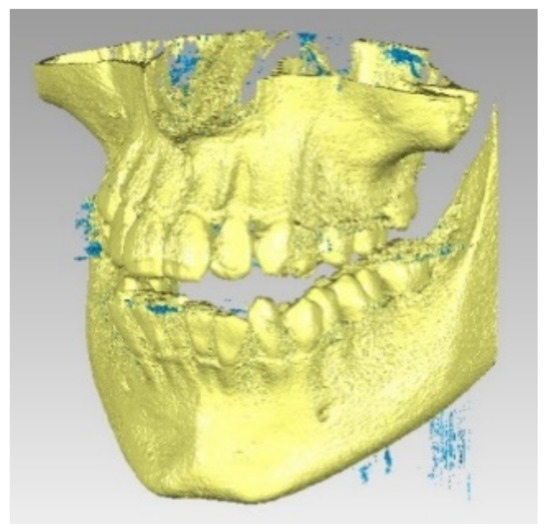

The final model of the osseous components was constructed in Geomagic and then in SolidWorks, where it was automatically transformed into a virtual solid (see Figure 9).

Finally, we imported the model in SolidWorks, where we transformed it into independent virtual solids. To obtain the complete model, we loaded the two models (osseous and dental) into the Assembly module of SolidWorks. Given that these models have a common global coordinate system because they come from the same set of CBCT images, we aligned the main planes that define the coordinate system and obtained the model shown in Figure 11.

Figure 9. The final model of osseous components in Geomagic (a) and SolidWorks (b).

Figure 11. Complete structure—two viewing modes (a,b).